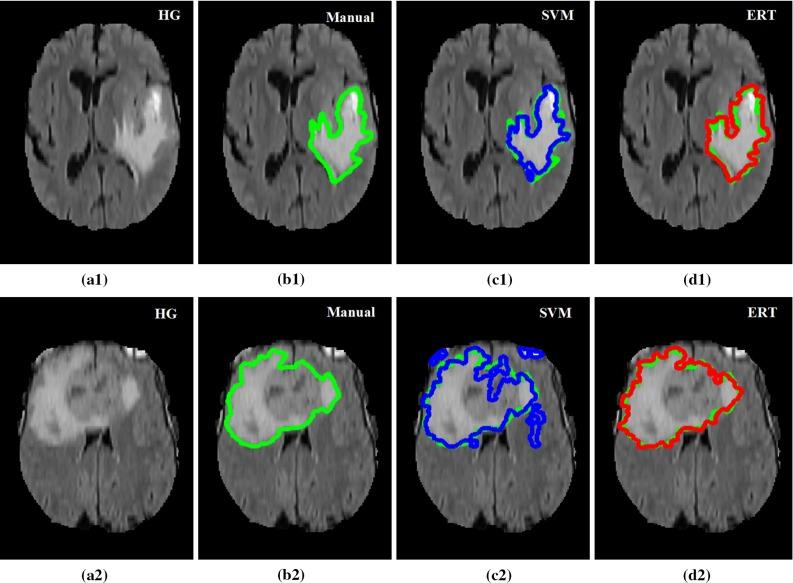

The method is based on superpixel technique and classification of each superpixel. A number of novel image features including intensity-based, Gabor textons, fractal analysis and curvatures are calculated from each superpixel within the entire brain area in FLAIR MRI to ensure a robust classification. Extremely randomized trees (ERT) classifier is compared with support vector machine (SVM) to classify each superpixel into tumour and non-tumour.

The proposed method is evaluated on two datasets: (1) Our own clinical dataset: 19 MRI FLAIR images of patients with gliomas of grade II to IV, and (2) BRATS 2012 dataset: 30 FLAIR images with 10 low-grade and 20 high-grade gliomas. The experimental results demonstrate the high detection and segmentation performance of the proposed method using ERT classifier. For our own cohort, the average detection sensitivity, balanced error rate and the Dice overlap measure for the segmented tumour against the ground truth are 89.48 %, 6 % and 0.91, respectively, while, for the BRATS dataset, the corresponding evaluation results are 88.09 %, 6 % and 0.88, respectively.

在两个数据集上对所提出的方法进行了评估:(1)我们自己的临床数据集:19例II至IV级胶质瘤患者的MRI FLAIR图像,以及(2)BRATS 2012数据集:30张FLAIR图像,其中有10例低级别胶质瘤和20例高级别胶质瘤。实验结果表明,使用ERT分类器的所提出方法具有较高的检测和分割性能。对于我们自己的队列,分割肿瘤相对于真实情况的平均检测灵敏度、平衡错误率和Dice重叠度量分别为89.48%、6%和0.91,而对于BRATS数据集,相应的评估结果分别为88.09%、6%和0.88。